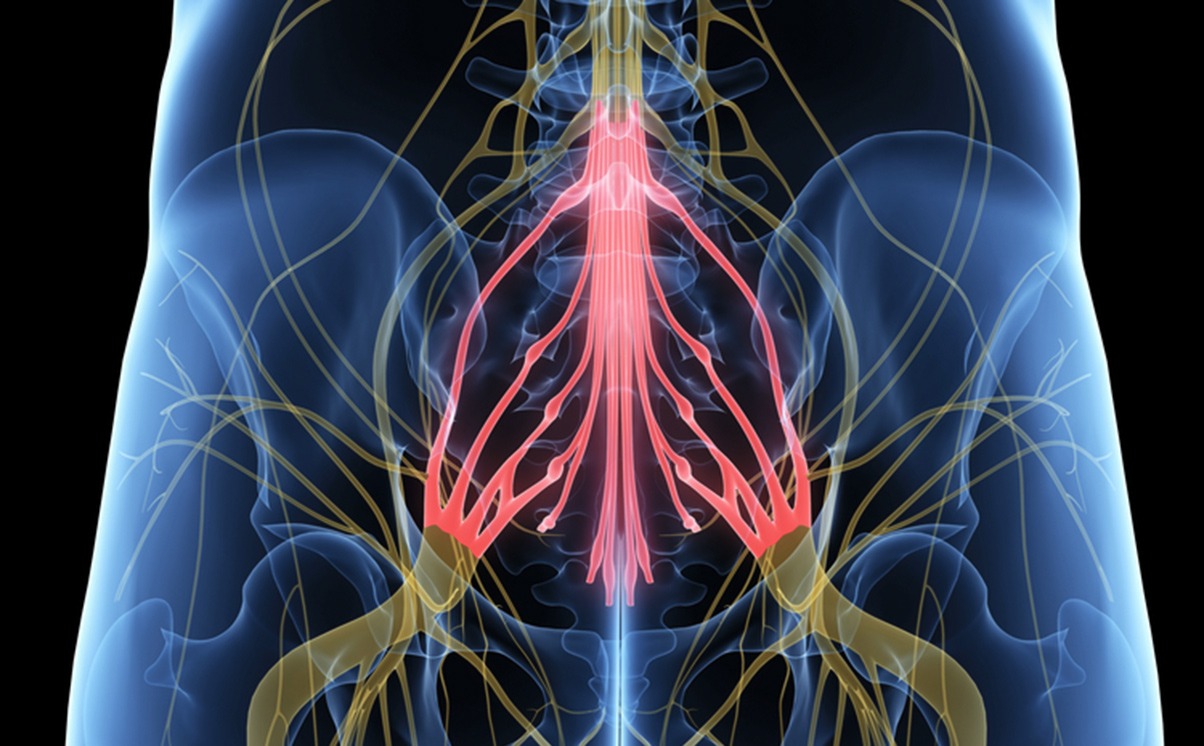

Cauda Equina Syndrome (CES) is a very rare but serious condition, where the bundle of nerves called the Cauda Equina at the bottom of the spine get compressed. The Cauda Equina control the function of the bladder and bowel, and the sensation to the skin of the genitals and bottom area. CES most commonly results from a massive herniated disc in the lumbar region but can also be caused by spinal lesions and tumours, spinal infections or inflammation and other less common conditions.

Red flag symptoms can include:

- Sciatica in both legs

- motor weakness and/or sensory loss in both legs

- anal and/or buttock numbness

- loss of feeling between the legs (saddle anaesthesia)

- bladder retention and/or incontinence

- bowel disturbance/incontinence

- erectile dysfunction